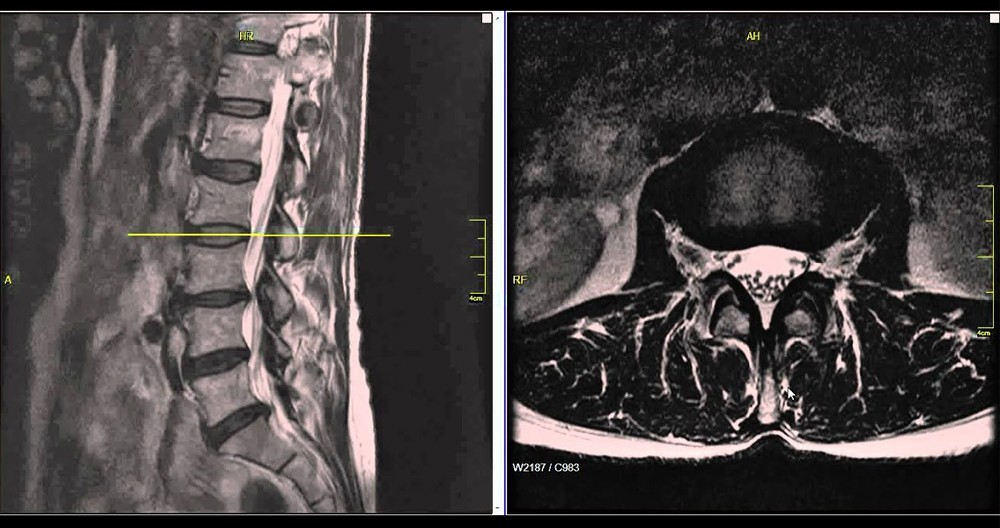

人类自从进化到站立行走以后,我们的腰椎成为了支撑躯干的中心。无论是站立还是坐位,腰部承受了60%以上的体重。腰椎老化退变成为了现代人面临的一大问题。根据卫生部的统计数据,我国腰椎疾病患者人数已经超过了2亿,成年人腰椎病发病率分别为80%,男女比例为3:1,20-40岁的患者占到了64%以上的比例。其中腰椎间盘突出症(腰突症)患者人数占全国总人数的15.2%,每100人就有15人患病。发病率仅次于感冒。

对于腰椎间盘突出症患者来说,非手术的治疗方法是首选。80%的人可以通过理疗、牵引、静卧休养和药物治疗来自我缓解。一般,经过3个月的保守治疗以后,如果状况不见好转或反而加重了,很有可能医生会建议手术。

外科手术,作为椎间盘突出症的最后治疗手段并不总是解决问题的最佳方法。其实,任何椎间盘突出切除术都会对椎间盘和邻近的部分组织造成难以避免的创伤。特别是病状还没有发展到一定要做手术的状况。在这种情况下手术的破坏程度往往要超过病状带来的危害。椎间孔镜微创手术也不列外,要摘除椎间盘突出来的部分,纤维环内肯定会留下一个相当大的窟窿,而连纤维环内最微小的裂隙都有可能引起椎间免疫反应和炎症,所谓的盘渗漏综合征。不过,保守治疗无效而症状已经无法忍受的情况下,还有什么选择呢?有没有更合理的治疗方法来解除腰病人士的痛苦?美国脊柱外科医生Dr. Kevin Pauza也同样思考过这些问题,最终研发了Discseel®Procedure・DST椎间盘修复再生术。

DST疗法是由美国脊椎外科医生及其团队研发的,自2010年开始应用于临床手术治疗。截止到2023年6月,已经治疗了8000余病例。目前,在亚洲地区,只有日本的野中腰椎医院拥有官方授权。Discseel® Procedure・DST椎间盘修复再生治疗与外科手术不同,不进行开刀,只需通过0.8mm的穿刺针插入椎间盘,注射生理制剂。注入的生理制剂不仅能够修补受损的纤维环,阻止髓核流出,还能促进盘内组织再生,使椎间盘恢复一定的弹性,从根本上治疗椎间盘,达到缓解症状的目的。Discseel®Procedure・DST椎间盘修复再生术可当天出院,而且适用于其他手术失败或复发的患者,甚至适合80多岁高龄的患者。此外,DST椎间盘修复再生疗法的复发率低,有效率高达70%以上。